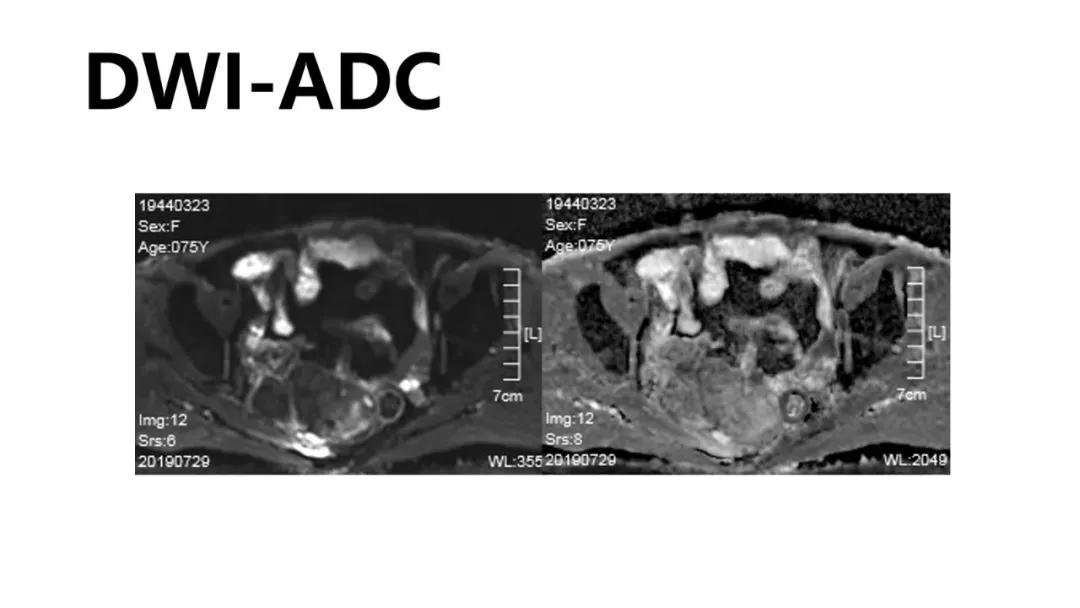

病例10

女,39 岁,体检发现盆腔肿块1月余

CA125:51U/ml

病理:左侧卵巢卵泡膜-纤维瘤